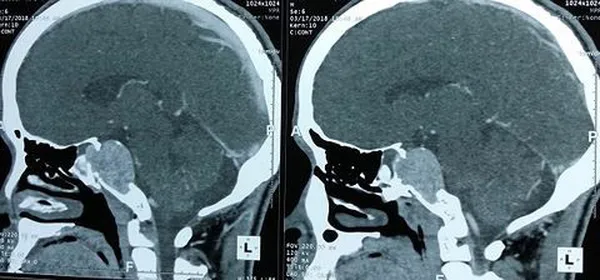

Theo người nhà bệnh nhân, anh B. đã đau đầu nhiều tháng nay nhưng không thăm khám mà chỉ uống thuốc. Đến khi bệnh nhân bị đau đầu thường xuyên hơn thì mới nhập viện. Sau khi khám và làm các chỉ định tại BV K, kết quả cho thấy có khối u não kích thước lớn 3cm x 4cm ở nền sọ vùng dốc nền.

Các bác sĩ quyết định thực hiện phương pháp phẫu thuật nội soi qua mũi, nhằm đảm bảo lấy tối đa khối u và an toàn cho người bệnh. C

a phẫu thuật kéo dài suốt 4 giờ. Khối u được loại bỏ hoàn toàn mà không làm tổn thương cấu trúc não và động mạch cũng như các dây thần kinh sọ, không để lại sẹo mổ trên da đầu. Đến nay, bệnh nhân đã tỉnh táo và tiếp xúc tốt với mọi người.